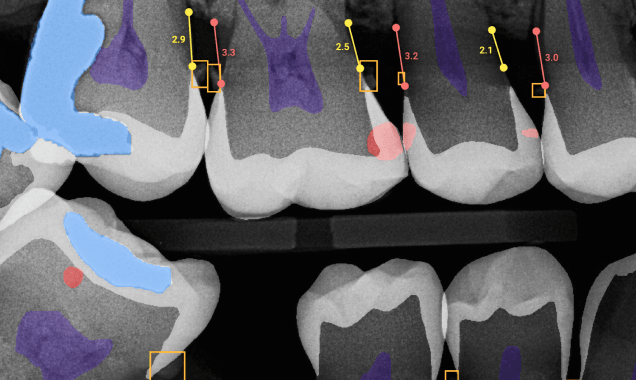

CareStack customers can now use Overjet to automatically analyze X-rays and effectively educate their patients, thanks to this integration.

Automatically analyzes the X-rays with AI